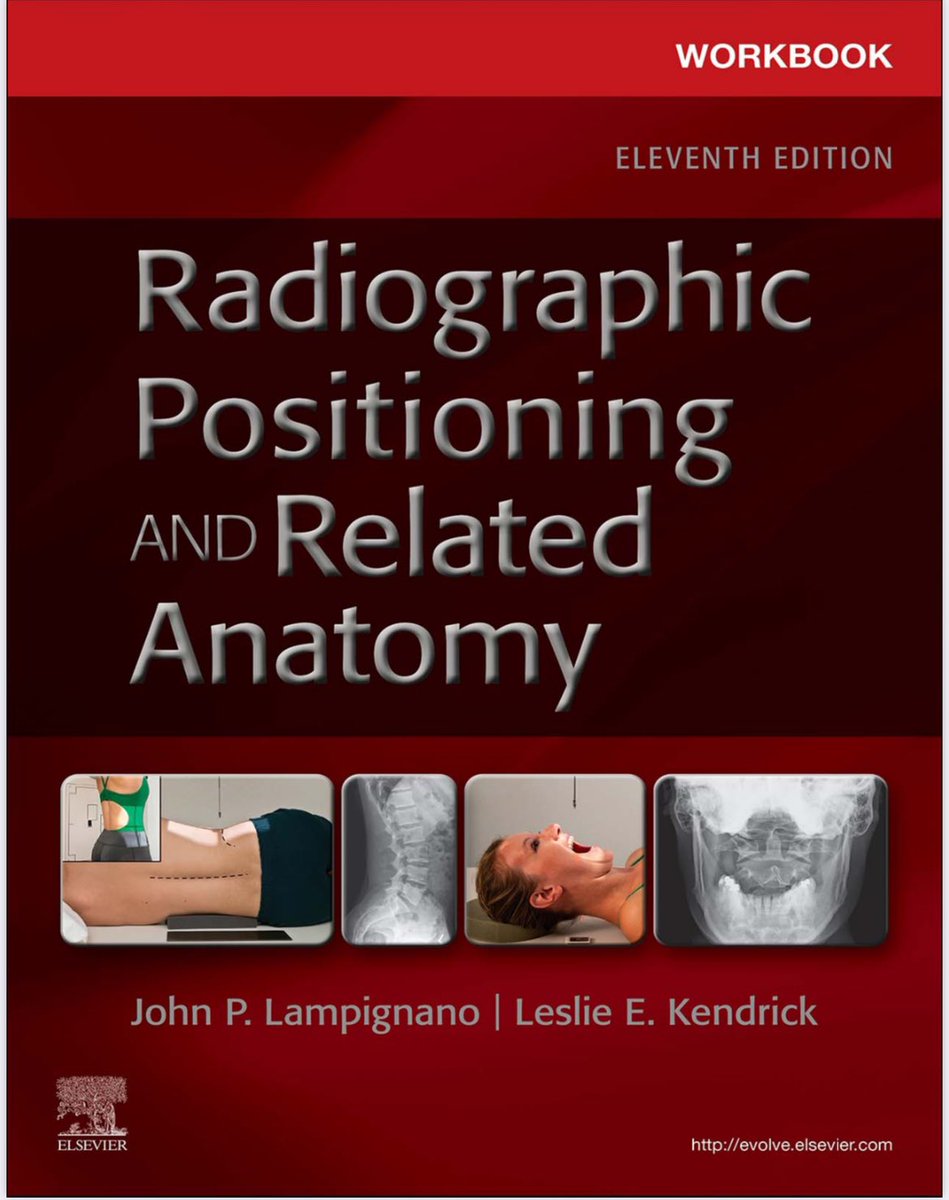

مرجع مميز للمهتمين في الأشعة العامة والتصوير الطبي

يفهمك الأوضاع التصويرة + وعلم الأمراض بطريقة واضحة وسلسلة بالإضافة إلى كتيب التدريب شامل لجميع الاسئلة الشائعة في مجال الأشعة

#radiology #radiography #xray #radiographer #radtech #srtle

من الاسئلة الاكثر أهمية في تصوير الركبة بالأشعة السينية فلنتشارك في الحل

SELF-TEST:

POSITIONING OF THE LOWER LIMB

Answer the following questions by selecting the best choice.

Reference (Merrill’s Atlas 12 edition)